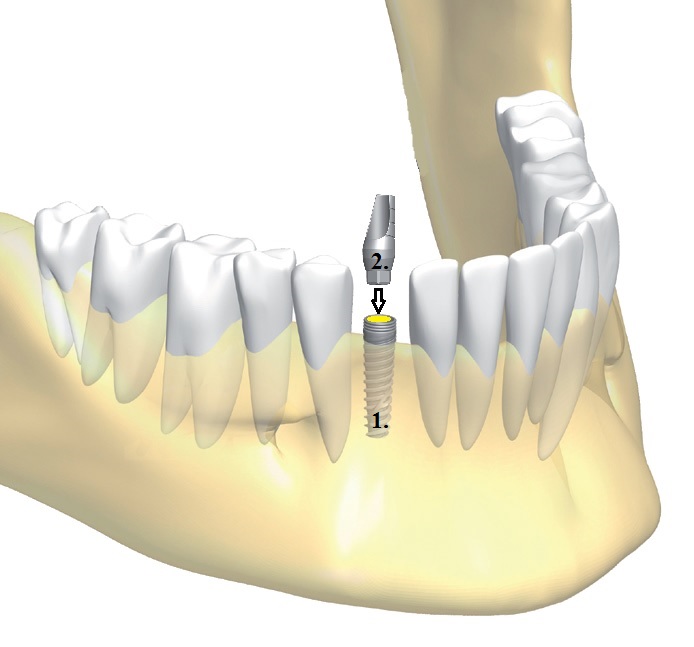

Mi az a fog implantátum?

A fog implantátum egy kis méretű titán csavar, egy biokompatibilis anyagból készült műgyökér, mely a hiányzó fog gyökerét helyettesíti és melyre aztán a fogpótlás kerül. A fogászati implantátumok tartós megoldást kínálnak a hiányzó fogak pótlására és egy alternatívát a protézis használatára. Napjainkban az implantátumok túlnyomó többsége színtiszta, ötvözetlen titánból készül. A titánt teljes mértékben elfogadja az emberi szervezet.

1. Műgyökér: ez maga az implantátum, melyet közvetlenül a csontba ültet az orvos

2. Felépítmény: a műgyökérbe illesztett elem, ez már kiemelkedik a csontból, erre kerül a fogtechnikus által készített korona